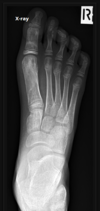

Fratura de Bennett

Fratura da base do primeiro metacarpo;

Intra-articular;

Dois fragmentos.